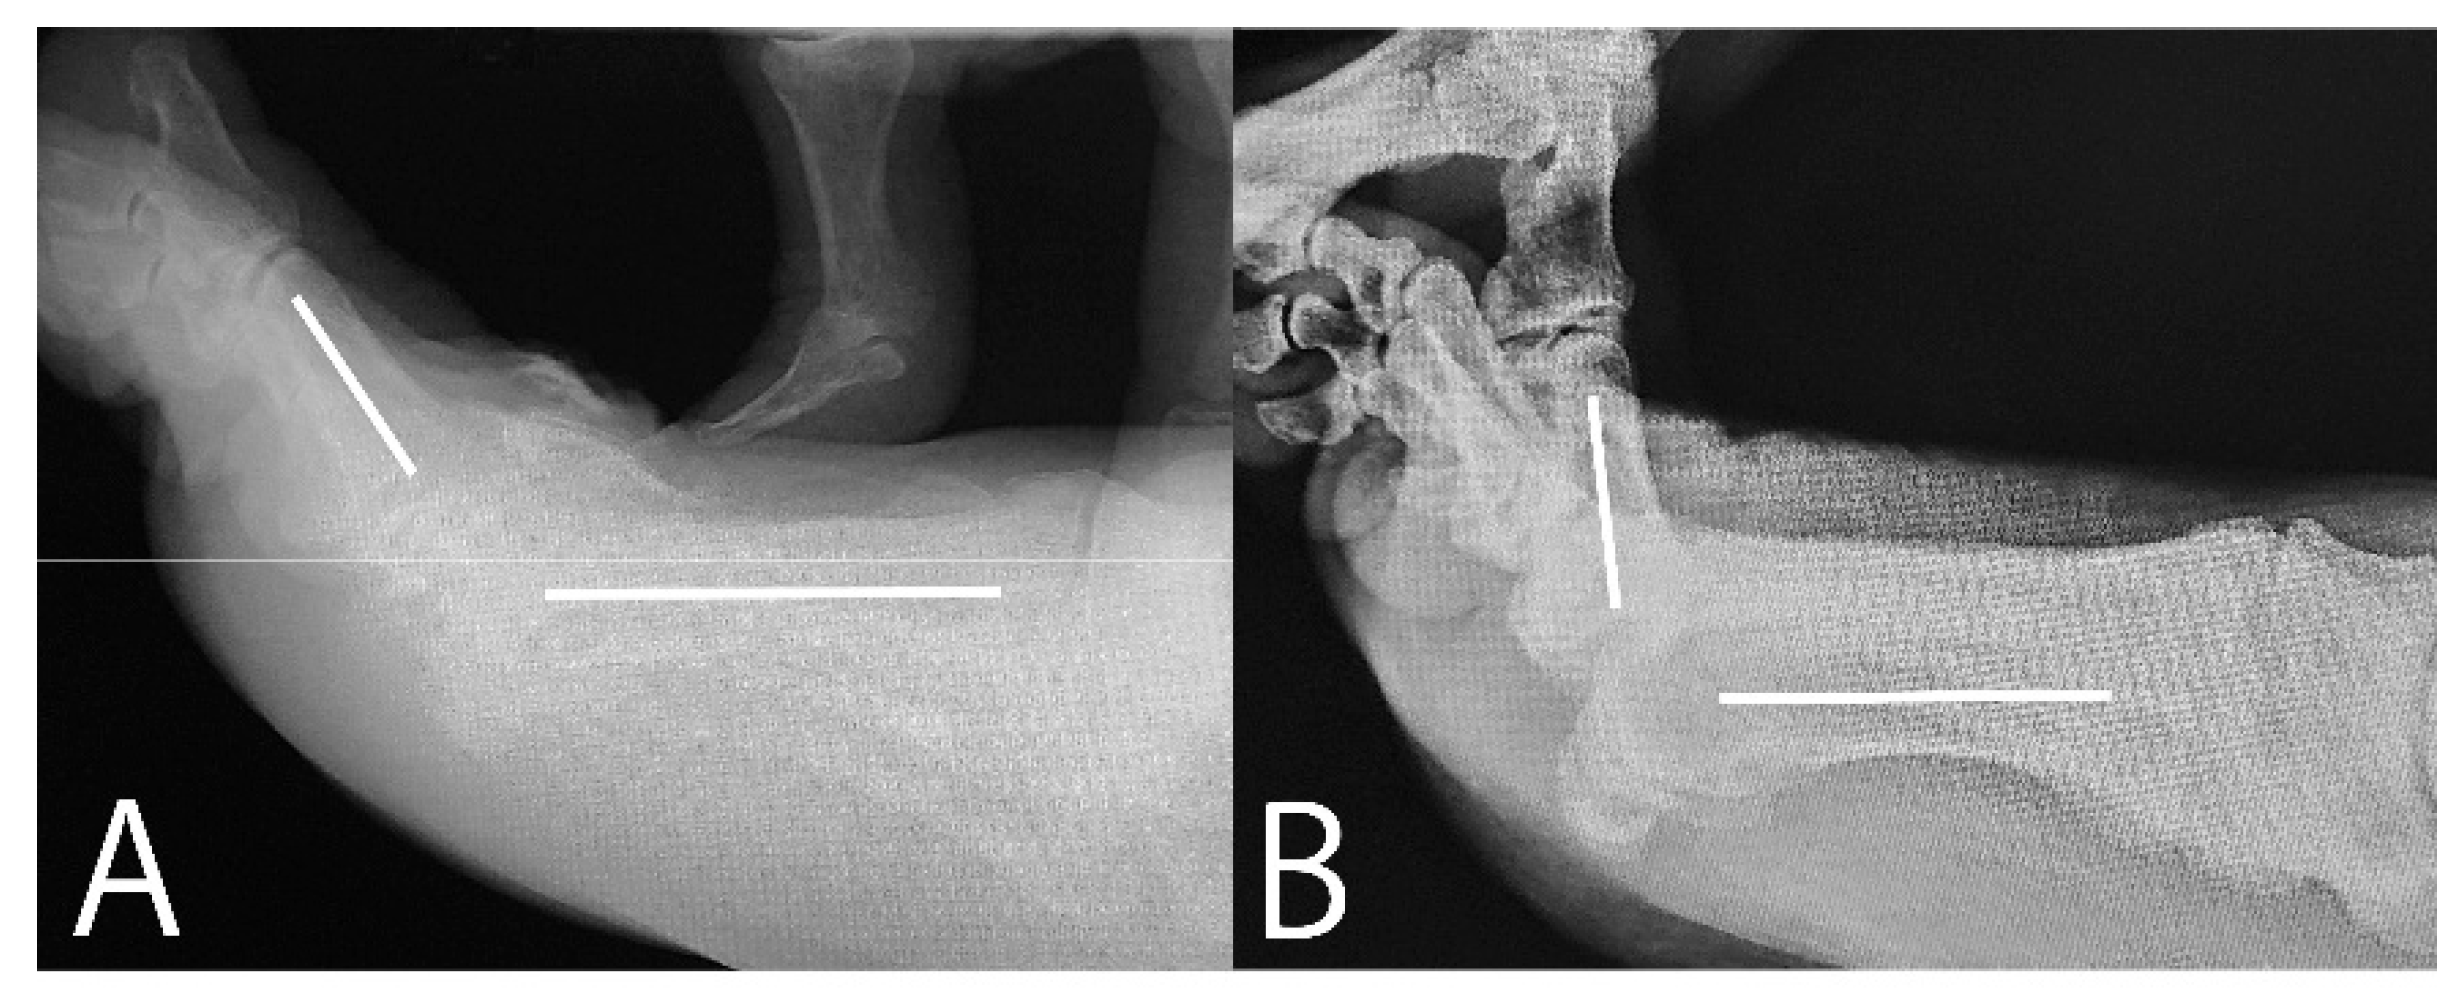

After releasing the FHB, the FHL tendon sheath wrapped in fat tissue became visible behind the residual void space (Figure 3C). The sheath was debrided to reveal the FHL tendon (Figure 3D). Once the FHL tendon was identified, the lateral plantar synovium and capsule were excised to expose the lateral FHB tendon. This tendon and plantar portion of the lateral ligament were then released using the small knife. The completeness of the plantar soft tissue release, which had restricted dorsiflexion, was confirmed arthroscopically as the hallux was dorsiflexed. The FHL tendon did not impede dorsiflexion (Figure 3E and 3F). The dorsiflexion improved from 55° to 85° (Figure 4).

Figure 4. Preoperative and intraoperative radiographs. (A) Preoperative radiograph; the dorsiflexion angle was 55°. (B) Intraoperative radiograph after releasing the flexor hallucis brevis tendon and plantar capsule; the dorsiflexion angle was 85.